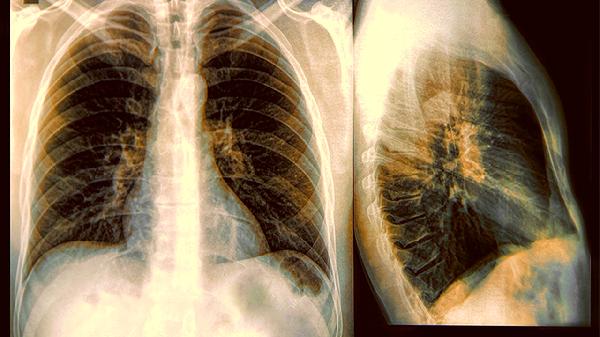

二、身体发出的求助信号别忽视

1.咳嗽超过三周要警惕

普通感冒咳嗽两周内会好转,如果干咳持续一个月以上,特别是夜间加重伴胸闷,可能是慢阻肺或哮喘的前兆。